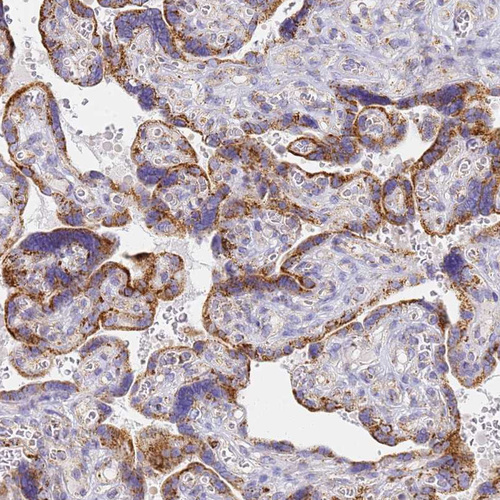

Immunohistochemical staining of human bronchus shows strong cytoplasmic granular positivity in respiratory epithelial cells.